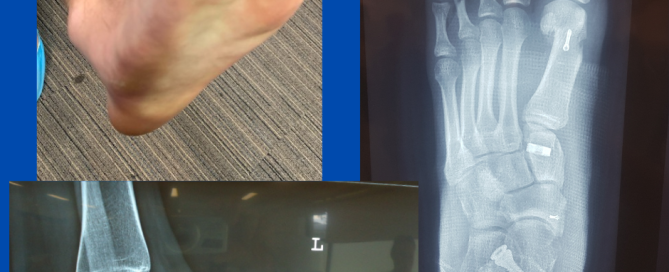

Subungual exostoses

Blog's main page This is one of a few subungual exostoses I see regularly throughout the year. Often when I see these cases, they have been treated as an ingrown [...]